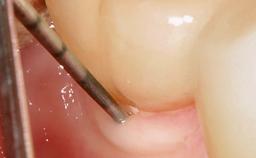

Treatment of Advanced Peri-Implantitis by Implant Removal Followed by Bone Reconstruction and New Implant Placement

Paolo Casentini and Matteo Chiapasco present a case in which the peri-implant defect was not suitable for a fully regenerative approach. It involves implant removal, use of a CAD/CAM customized titanium mesh in the grafting phase, and placement of new implants. A 62-year-old woman was referred for consultation regarding her implant-supported prosthesis replacing teeth 14 to 16. The patient’s main concern was pain and recurrent swelling in the right posterior maxilla. The patient also reported difficulty and discomfort when brushing the area. The patient reported she had been treated in another country, where she had received three implants in combination with sinus-floor augmentation for the replacement of the posterior maxillary teeth three years earlier. The patient indicated “endodontic complications” to be the reason for the extraction of the teeth.